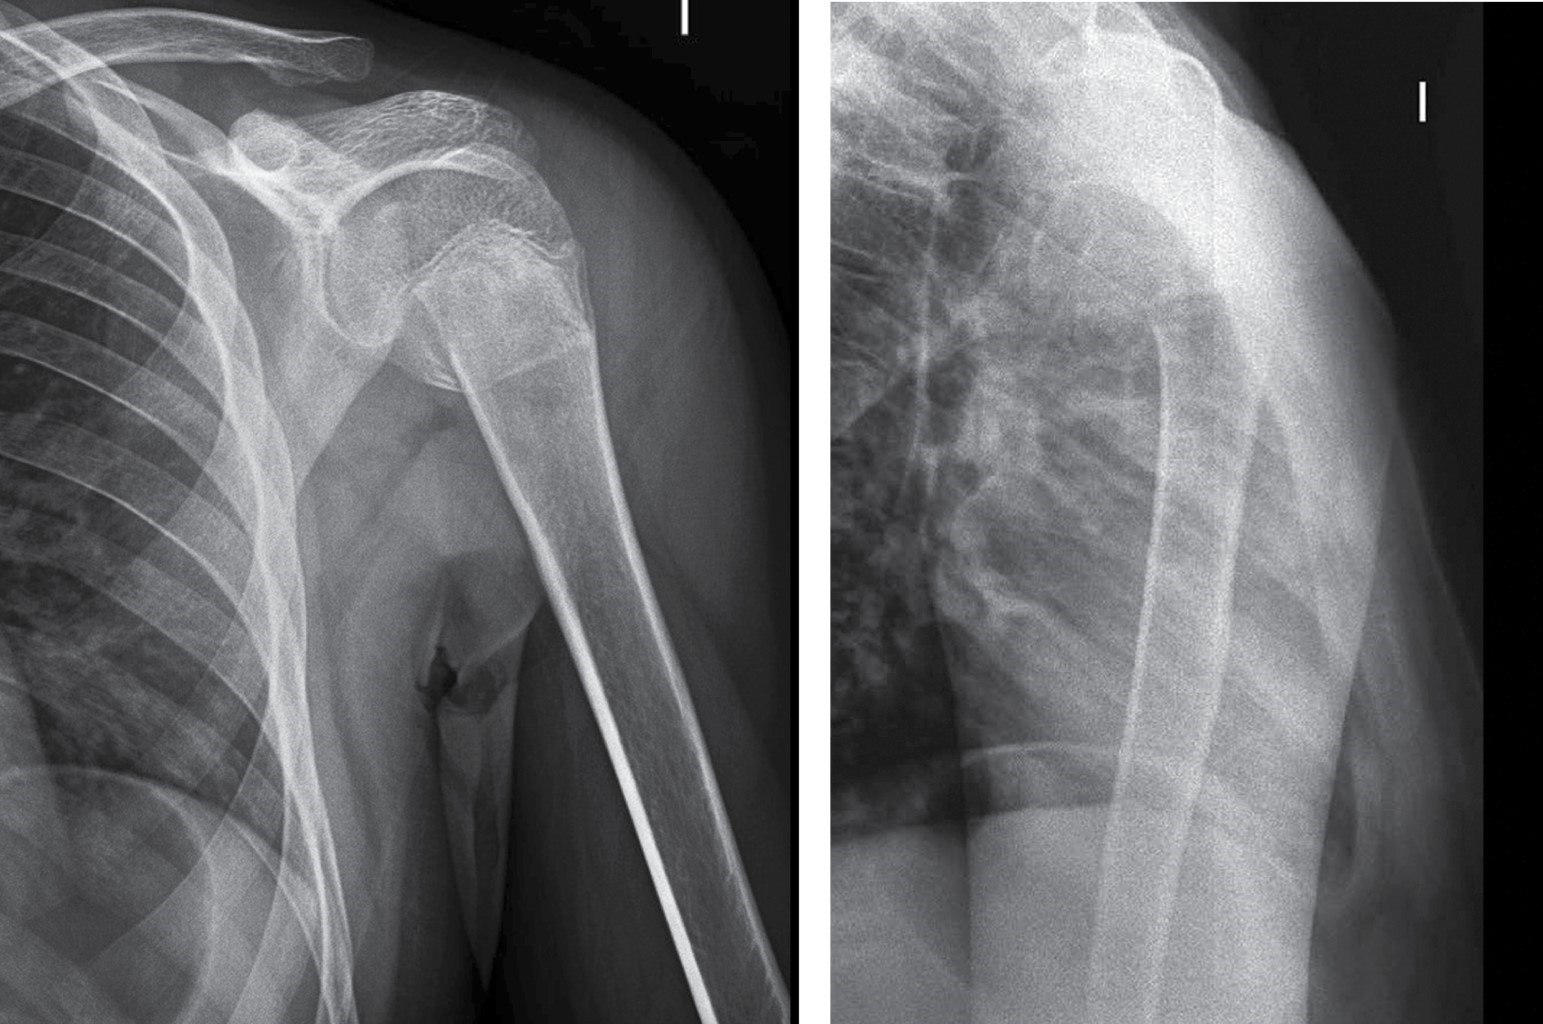

Masculino 13 años – Fractura de extremo proximal de húmero Neer-Horowitz tipo III (Figura 3).

• 1. Tratamiento conservador – Dra. Laura Montes Medina (SEOP):

Las fracturas de húmero proximal en niños y adolescentes tienen una baja incidencia, representando aproximadamente 2% de todas las fracturas pediátricas.61,66 La mayoría de estas fracturas se presentan sin desplazamiento o mínimamente desplazadas, pudiendo ser tratadas en forma incruenta gracias al gran potencial de remodelación que presenta el húmero proximal.67 Sin embargo, no existe consenso con respecto al tratamiento de fracturas con mayor desplazamiento en pacientes que se encuentran más cercanos a la madurez esquelética. Quienes favorecen el tratamiento conservador argumentan que la fisis proximal del húmero es de las más activas y que la articulación glenohumeral es la articulación más móvil del cuerpo, pudiendo compensar cierta cantidad de deformidad residual. Sin embargo, el tratamiento óptimo en última instancia debe depender del potencial de remodelación (edad ósea), la magnitud de la deformidad, comorbilidades y las demandas funcionales del paciente.